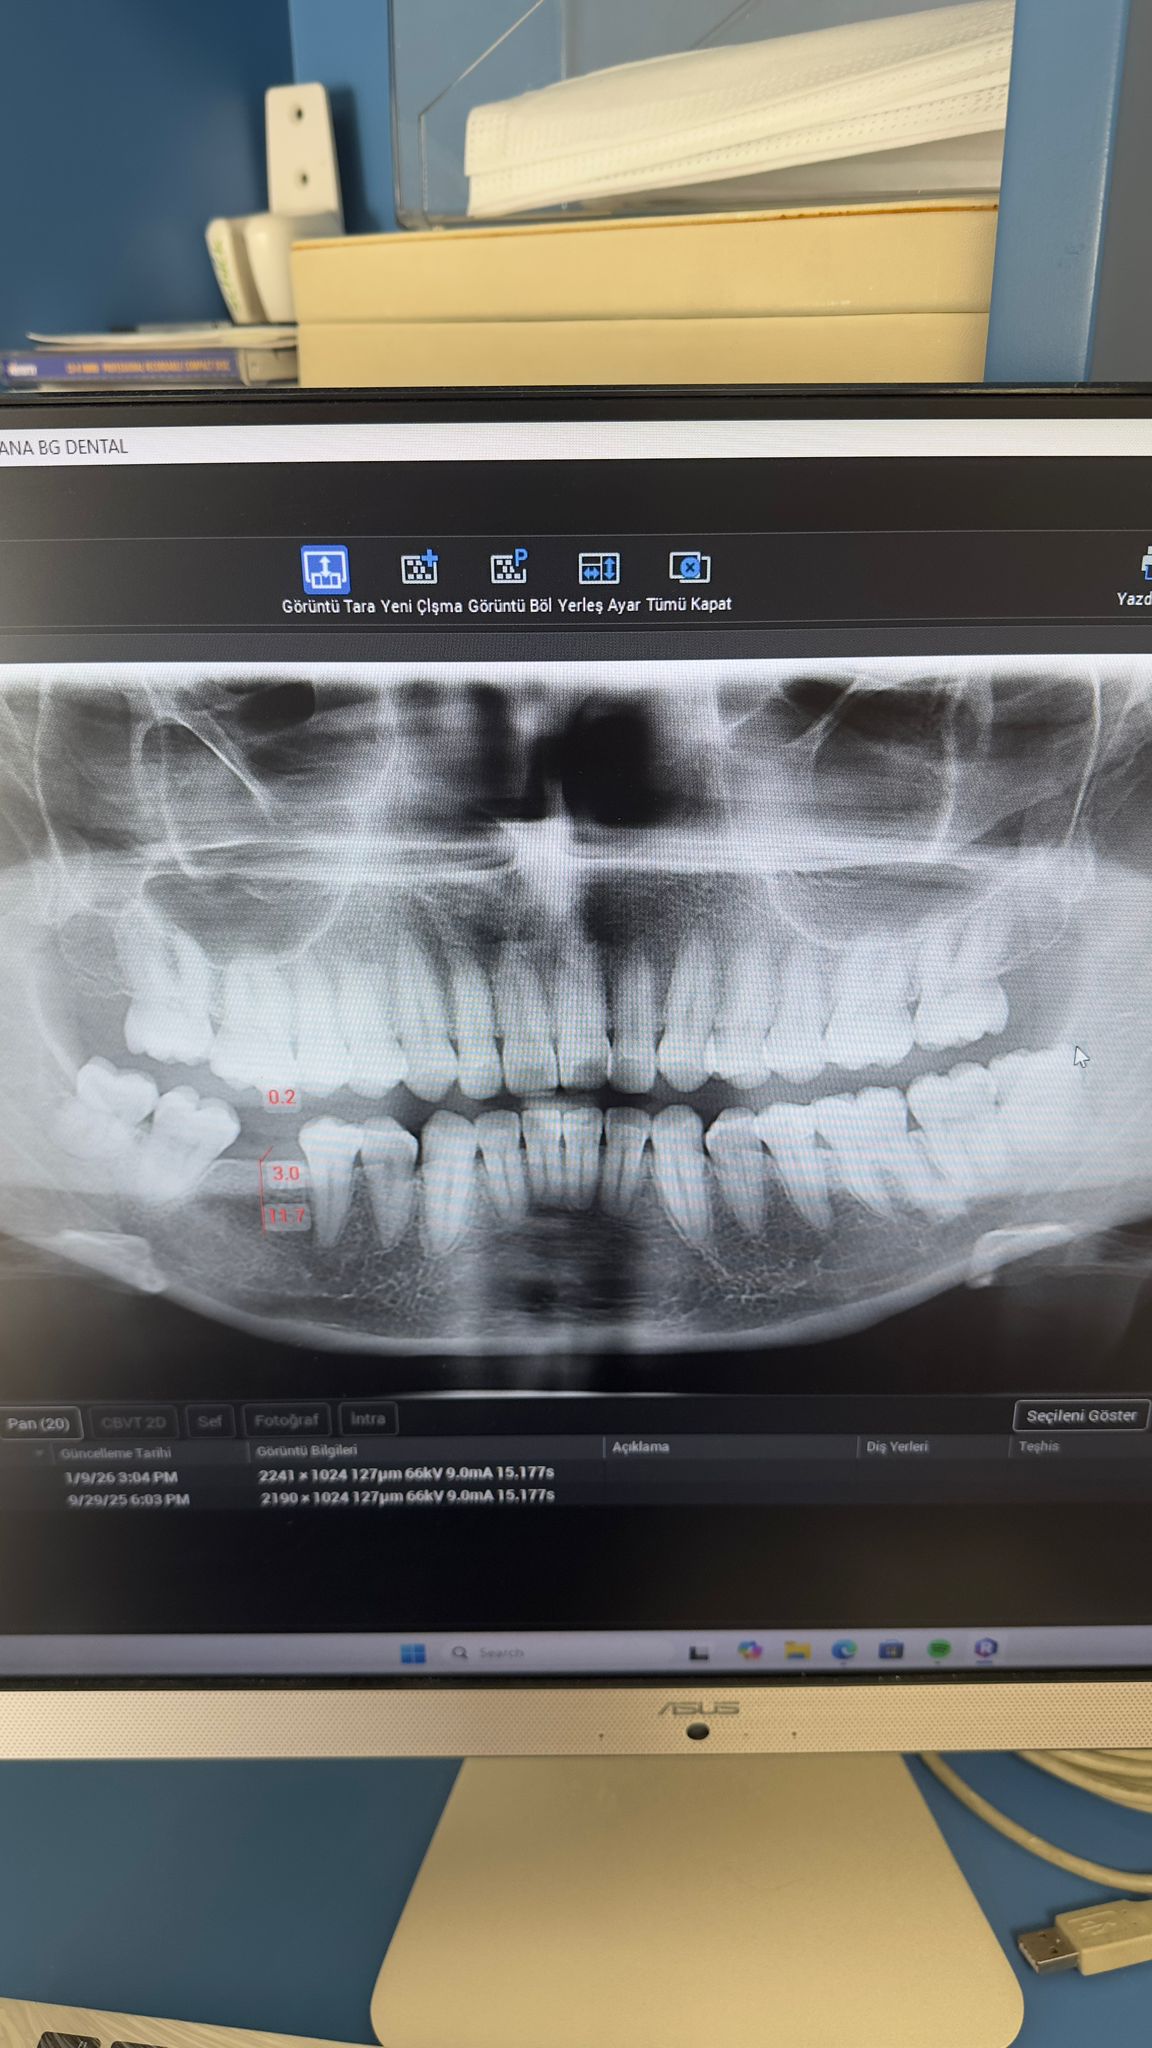

Ali Akıllıoğlu ( 01.09.1968) muayene edilip, panoramik film çekilmiştir. Alt ön bölgedeki 4 kesici dişinin sallandığı tespit edilmiştir. Kalp hastası olduğu için doktorundan lokal anestezi altında cerrahi işlem yapılabilmesi için görüş alınmıştır. Alt dört keser dişi çekilip , yan keserler bölgesine iki adt 3,2 mm çapında implant yerleştirilmiştir. Şimdi implantların osseintegrasyonu için beklenmektedir.3 Ekim 2025te muayene edildi. 07 Ocak 2026 da implantlar yerleştirildi.

Hastanın sağ üst ve alt 1. büyük azı dişlerinin eksik olduğu tespit edilmiştir. Gerekli muayene ve tetkikler yapıldıktan sonra sağ üste 3.7 mm, sağ alta 4 mm çapında iki implant yerleştirilmiştir. Osteointegrasyon için beklenmektedir. 29 Eylül muayene 13 Ocak implantlar yerleştirildi.

Nesrin Bat ( 01.02.1993) Muayene sonrası alt sağ 1. büyük azı dişinin eksik olduğu tesbit edilmiştir. Gerekli tetkikler sonrasında 3.7 mm çapında bir implant yerleştilmiştir. Osteointegrasyon için beklenmektedir. 29 Eylül Muayene 13 Ocak implant yerleştirildi.

Kulüp olanaklarımız ile 3 hastada 5 implant ve bunların üst ünitelerinin takılması sağlandı